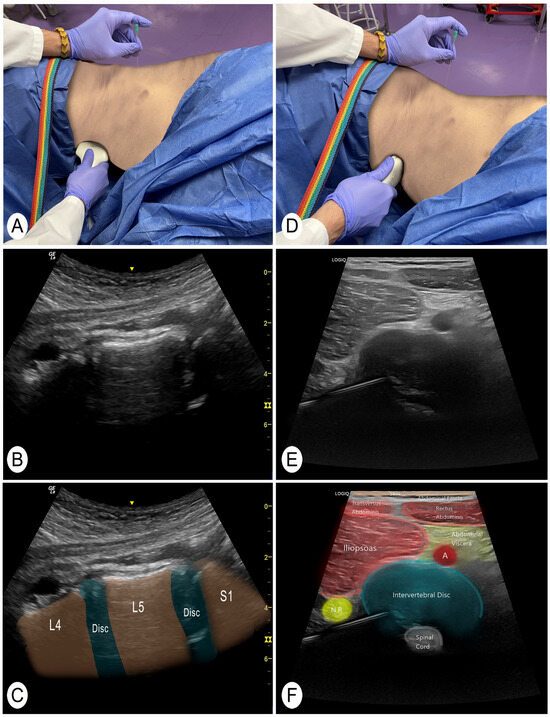

2.3. Ultrasound-Guided Needling Approach

| L1 (n = 12) | L2 (n = 12) | L3 (n = 12) | L4 (n = 12) | L5 (n = 12) | Global (n = 60) | |

|---|---|---|---|---|---|---|

| Length of the needle introduced (mm) | 75 ± 9 | 73 ± 15 | 81 ± 12 | 86 ± 16 | 81 ± 18 | 79 ± 15 |

| Angulation of the needle (°) | 134.9 ± 23.8 | 137.7 ± 14.3 | 131.0 ± 20.4 | 124.5 ± 18.8 | 116.7 ± 15.3 | 129.0 ± 20.2 |

| Reach the posterolateral part of the discs | 91.7% | 100% | 100% | 91.7% | 83.3% | 93.3% |

| Distance from the vertebral spine to the needle (mm) | 80 ± 15 | 78 ± 15 | 83 ± 22 | 77 ± 23 | 67 ± 20 | 77 ± 19 |

| Distance of the needle to the main nerve roots (mm) | 2.1 ± 0.6 | 2.2 ± 0.8 | 2.3 ± 2.0 | 1.8 ± 1.0 | 1.6 ± 0.7 | 2.0 ± 1.2 |

| Unwanted structures crossed | - | - | - | - | 1 nerve root | 1 nerve root |